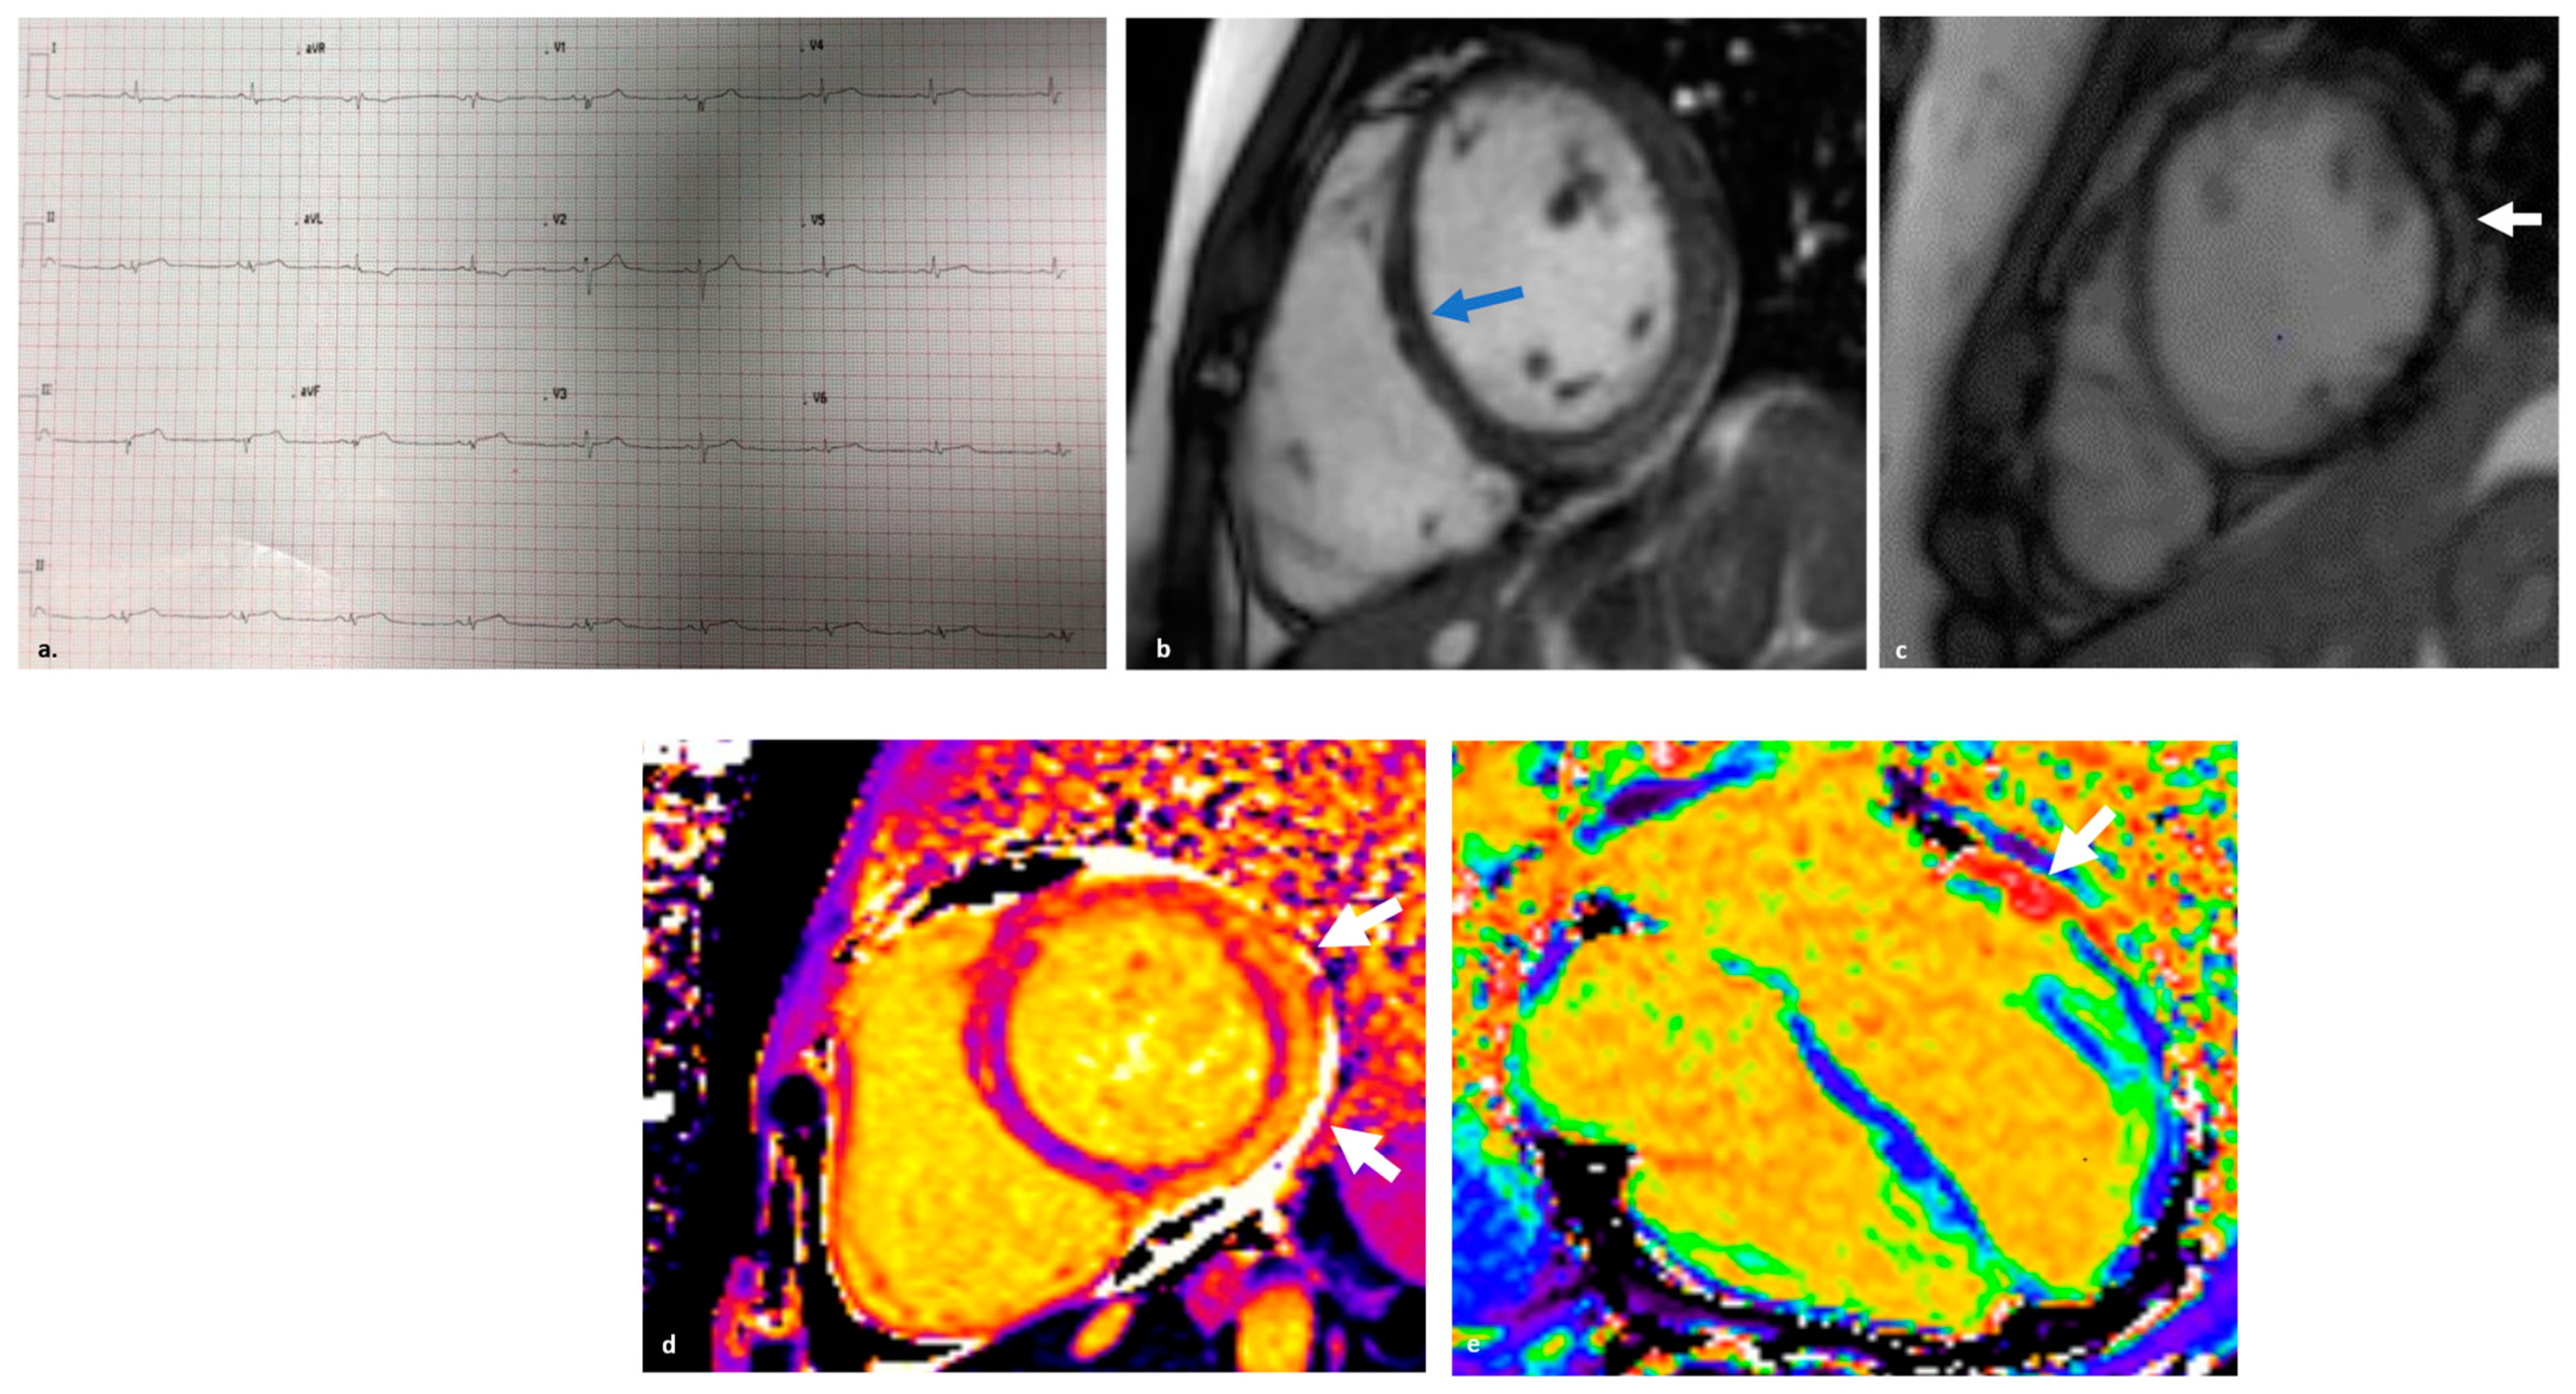

2.1. Definition and Diagnosis

3.2. Clinical Features and Diagnosis

4.2.2. Diagnostics

4.5.2. Diagnostics

5.2. Clinical Findings and Genetics